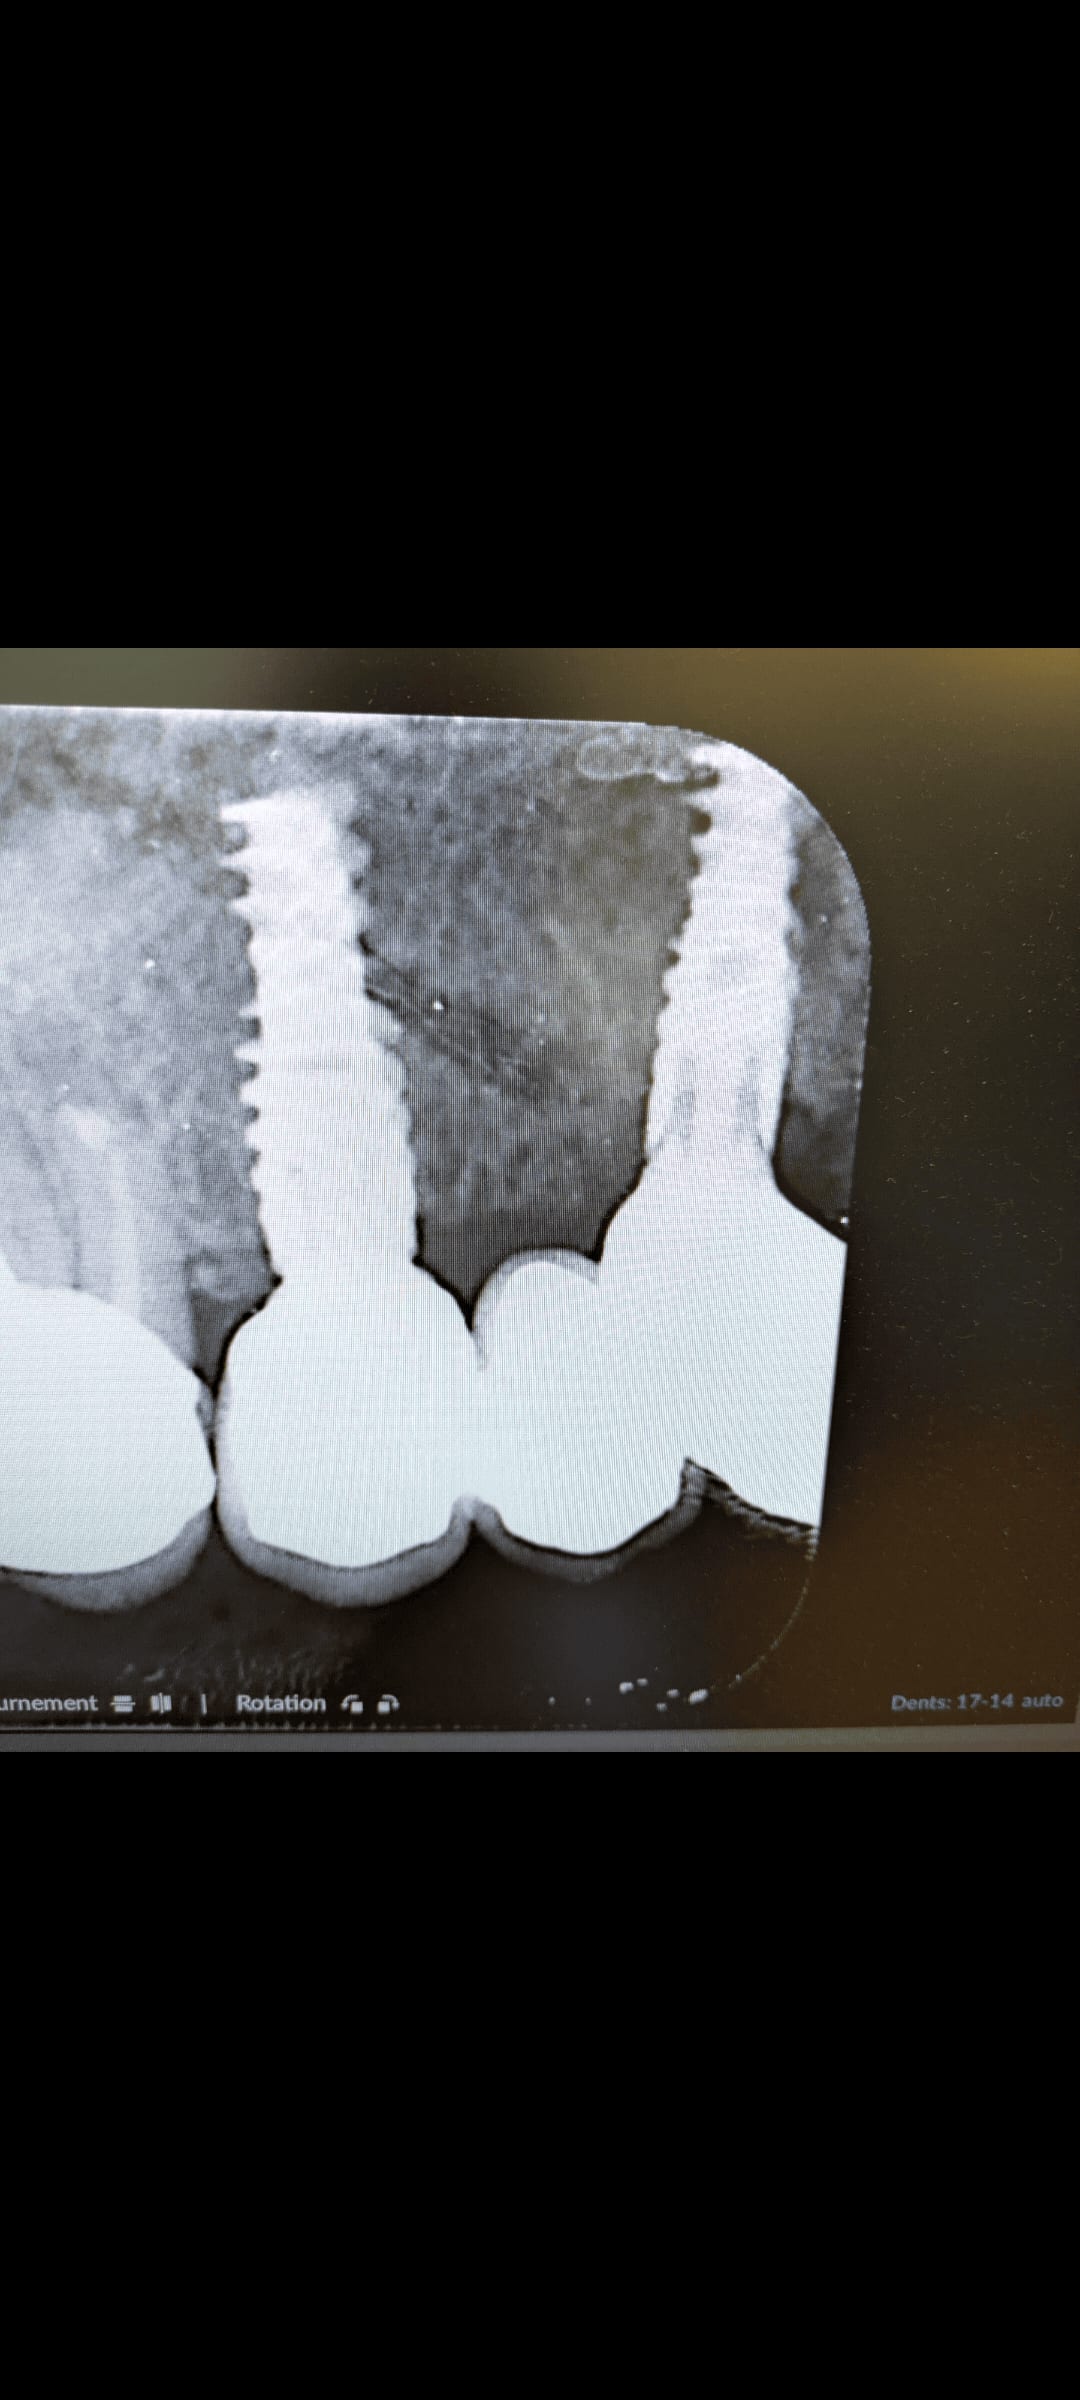

Nouvelle patiente, envoyée par un implanto avec qui je travaille ponctuellement, parce que sa dentiste habituelle n'exerce plus. Elle vient avec 2 implants Nobel en 13 et 15 (mais l'implant en 13 est plutôt entre 13 et 14...). Je fais l'empreinte numérique pour un bridge.

Mon prothésiste me fait ce qu'il peut niveau esthétique comme l'implant en 13 est très distalé mais ca passe esthétiquement. Il a pris une base universelle non engageante en 13 (Nobel) et une base classique engageante en 15 (Nobel). Rien à signaler à l'essayage + radio. Puis au moment de visser à 35Ncm comme indiqué sur l'emballage de la base, j'ai l'impression de devoir forcer un peu avec la clef dynamo (Nobel), en tout cas c'est pas comme d'habitude, jusqu'à un énorme craquement. Coup de chaud +++ je dévisse en 15 et la base reste dans l'implant en 13.

on voit sur ta photo prenom et date de naissance de la patiente + des noms de patients en arriere plan de ta retro sur l'agenda

croc1765 écrivait:

Merci... Vraiment pas fait exprès, trop concentrée sur le problème d'implant. J'ai modifié